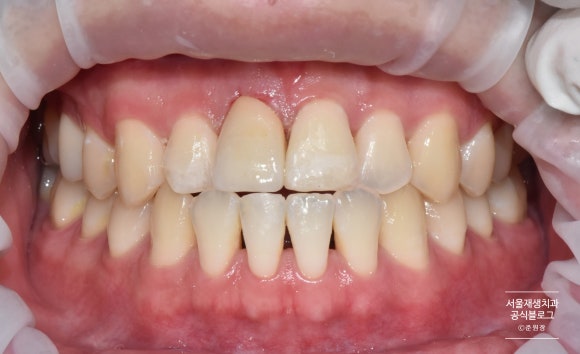

크라운 부착과 심미레진수복

짠! 자연치아보다 더 매끈하고 반짝거리는 크라운이 도착했습니다.

어떤 것이 자연치아였는지 제가 봐도 헷갈리네요^^

파절되어 있던 양 옆 치아와 아래치아도 레진을 이용하여 당일에 심미수복을 진행하였습니다.

치료 전 후 비교

치료 전 후 사진입니다.

꼬박 3주가 걸린 과정이었습니다.

매번 예약시간도 준수해주시고, 의료진과 스텝들을 늘 배려해주셔서 감사드립니다.

외상받은 치아는 현재 불편함이 없더라도, 수개월, 수년이 지나 비로소 증상이 발생하는 경우가 많이 있습니다.

앞으로도 꾸준한 검사와 관리로 자연치아를 오래 유지할 수 있도록 도움드리겠습니다.